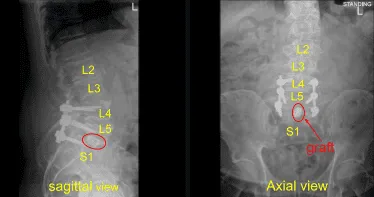

El interespacio estaba completamente irrigado. El autoinjerto morcelizado se empaquetó en el interespacio, y luego un separador intersomal expansible de titanio de 22 mm de largo fue suavemente prensado en el interespacio con un mazo. Se realizaron AP y fluoroscopia lateral para confirmar la posición y profundidad en la línea media; La jaula se amplió hasta la apretadura y la tensión adecuadas.

Se repitieron las radiografías para confirmar la posición y el tamaño correctos. Las señales de neuromonitorización se mantuvieron estables. A continuación, con el pedículo L5 izquierdo completamente aislado y expuesto, colocamos el tornillo pedicular izquierdo L5 decorificando con una canulación eléctrica de alta velocidad con el buscador curvo de pediculares Lenke a mano alzada palpando las brechas usando un tap de 5,0 mm y colocando sin dificultad un tornillo pedicular de titanio de 45 mm x 6,0 de diámetro.

Luego colocamos de forma similar un tornillo pedicular derecho L5 usando una técnica similar. Cubrimos al paciente de forma estéril y realizamos una tomografía computarizada intraoperatoria que mostró la correcta posición de todos los tornillos pediculares y el espaciador intersomal.

Se seleccionaron varillas de titanio precortadas y predelineadas que se colocaron sobre los tulipanes y se aseguraron con tapas de bloqueo, que se apretaron finalmente con dispositivos de torsión y antitorque en L4, L5 y S1. Autoinjertos de matriz ósea desmineralizada en morcelado recogidos de la descompresión, así como aloinjertos proteicos morfogénicos óseos, se empaquetaron en las canaletas laterales desde L4 hasta S1 y la artrodesis posterolateral.

Hicimos la AP final y radiografías laterales, que mostraron la posición correcta de todo el hardware. El cierre se dictará por separado. Al final del caso, el paciente fue colocado boca arriba en el carro y trasladado a la sala de recuperación en estado estable.